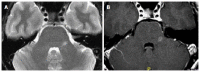

We describe common and less common diseases that can cause magnetic resonance signal abnormalities of middle cerebellar peduncles (MCP), offering a systematic approach correlating imaging findings with clinical clues and pathologic mechanisms. Myelin abnormalities, different types of edema or neurodegenerative processes, can cause areas of abnormal T2 signal, variable enhancement, and patterns of diffusivity of MCP. Pathologies such as demyelinating disorders or certain neurodegenerative entities (e.g., multiple system atrophy or fragile X-associated tremor-ataxia syndrome) appear to have predilection for MCP. Careful evaluation of concomitant imaging findings in the brain or brainstem; and focused correlation with key clinical findings such as immunosuppression for progressive multifocal leukoencephalopahty; hypertension, post-transplant status or high dose chemotherapy for posterior reversible encephalopathy; electrolyte disorders for myelinolysis or suspected toxic-drug related encephalopathy; would yield an appropriate and accurate differential diagnosis in the majority of cases.